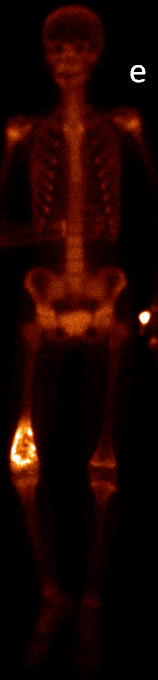

21.2.2. Bone metastasis

The most common indication of bone scintigraphy is the evaluation of bone metastasis. (Figure 5.)

Image

a

b

c

d

5. Multiplex bone metastases. Bone scintigraphy, anterior (a) and posterior (b) whole body scans. SPECT-CT sagittal plane, fusion image (c) and CT image (d). Obvious bone structural changes cannot be identified on the CT scan yet.

The examination is appropriate for staging a malignant process and following-up bone metastases. It is clinically most suitable for lesions that frequently present bone metastasis, primarily in case of prostate-, breast-, lung cancer and neuroblastoma. It is, however only indicated in cases where the soft tissue involvement of the tumor is big enough to suggest a higher incidence of bone metastasis; before radical surgeries and for the selection of patients who would benefit form a palliative radionuclide therapy. Otherwise, scintigraphy is advisable in case of any primary tumor, if the suspicion for metastasis is raised, e.g.: bone pain, pathologic radiological or lab results (elevated serum ALP and tumor marker levels). Bone metastases in most cases are located in bones that contain red bone marrow (skull, vertebrae, ribs, sternum, pelvic bones and the proximal bone segments of the limb) and usually show a multiplex appearance. Activity increase can be seen typically, metastases that cause activity decrease are rare; they could occur in cases of thyroid gland tumor, renal carcinoma, lymphoma and multiple myeloma. Solitary lesions or a few lesions only, due to the aspecific nature of the examination, cause a differential diagnostic problem in many cases, for example vertebral degenerative processes can mimic metastatic activity. Equivocal lesions usually require further, targeted radiological investigations. A negative X-ray examination does not rule out the possibility of a metastatic lesion, since the isotope scan is more sensitive. Therefore, it is possible that it could already be detecting an existing metastasis, while X-ray is still insensitive and unable to show the lesion. (Figure 5.)